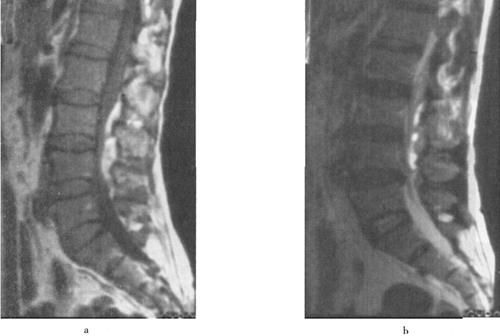

急性脊髓创伤常由于脊柱结构破坏(图7-12a和b),如撕裂伤、横断伤或严重挫伤,也可由内在的可逆性损伤如震荡或轻微挫伤引起,还可以由外来的可逆损伤如脊髓受压引起(图7-13)。按损伤程度分为脊髓震荡伤、脊髓挫伤、脊髓撕裂伤和横断伤。

图7-12a 颈段脊髓横断性损伤。颈椎正侧位片:C5以上前脱位,该水平段椎管狭窄,可推测脊髓受压迫

图7-12b MRI矢状面T1WI可见颈髓在C5水平明显受压,椎体前缘和椎管内可见中等偏高信号,局部颈髓可见斑点状高信号;12WI被压迫的脊髓亦见高信号出血灶,脊椎前方前纵韧带下血肿,呈高信号